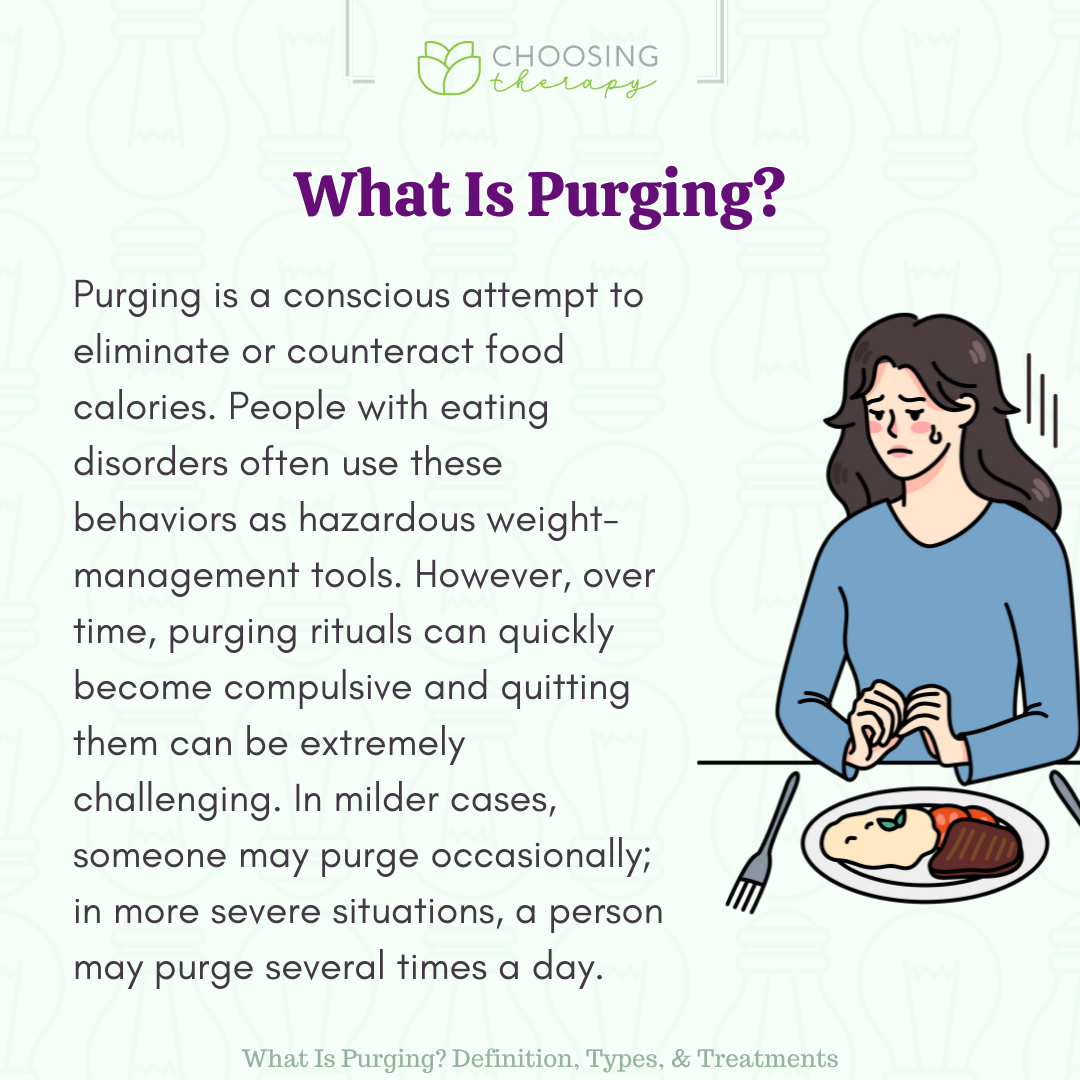

What Does Purging Mean

https://www.choosingtherapy.com/wp-content/uploads/2022/09/2-6.png